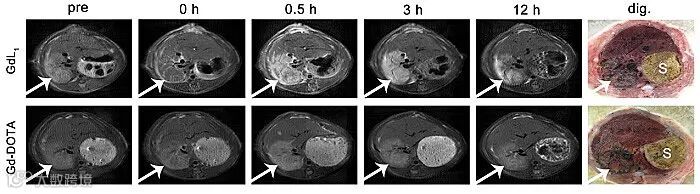

其中GdL1在体外显示了优异的磁共振性质,其弛豫率分别为7.28,显著高于临床上常用造影剂Gd-DOTA(4.28);并且具有很好的体外稳定性及水溶性。同时,从大鼠缺血再灌注肝坏死模型以及肌肉坏死模型的磁共振成像上可以看到,GdL1实现了对坏死肝脏和坏死肌肉的清晰在体成像,明显区分坏死组织与正常组织,显示出良好的坏死靶向性。

Figure 2. The MR images of rat models of reperfused liver infarction at pre-injection and 0 h, 0.5h, 3 h, 12 h post-injection of GdL1 (0.1 mmol/kg) and Gd-DOTA and corresponding macroscopic section. White arrow shows necrotic liver, S indicates stomach